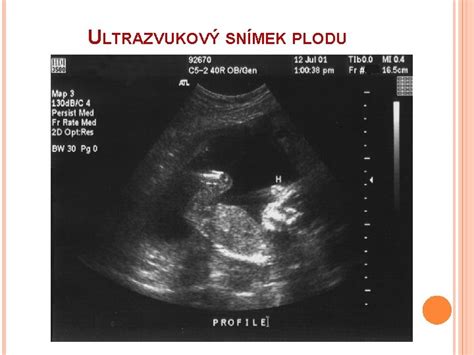

- Ultrazvukové vyšetrenie: Môže preukázať, či srdce bije a či sa plod hýbe. V prípade absencie srdcovej aktivity a pohybu je diagnóza úmrtia plodu potvrdená.